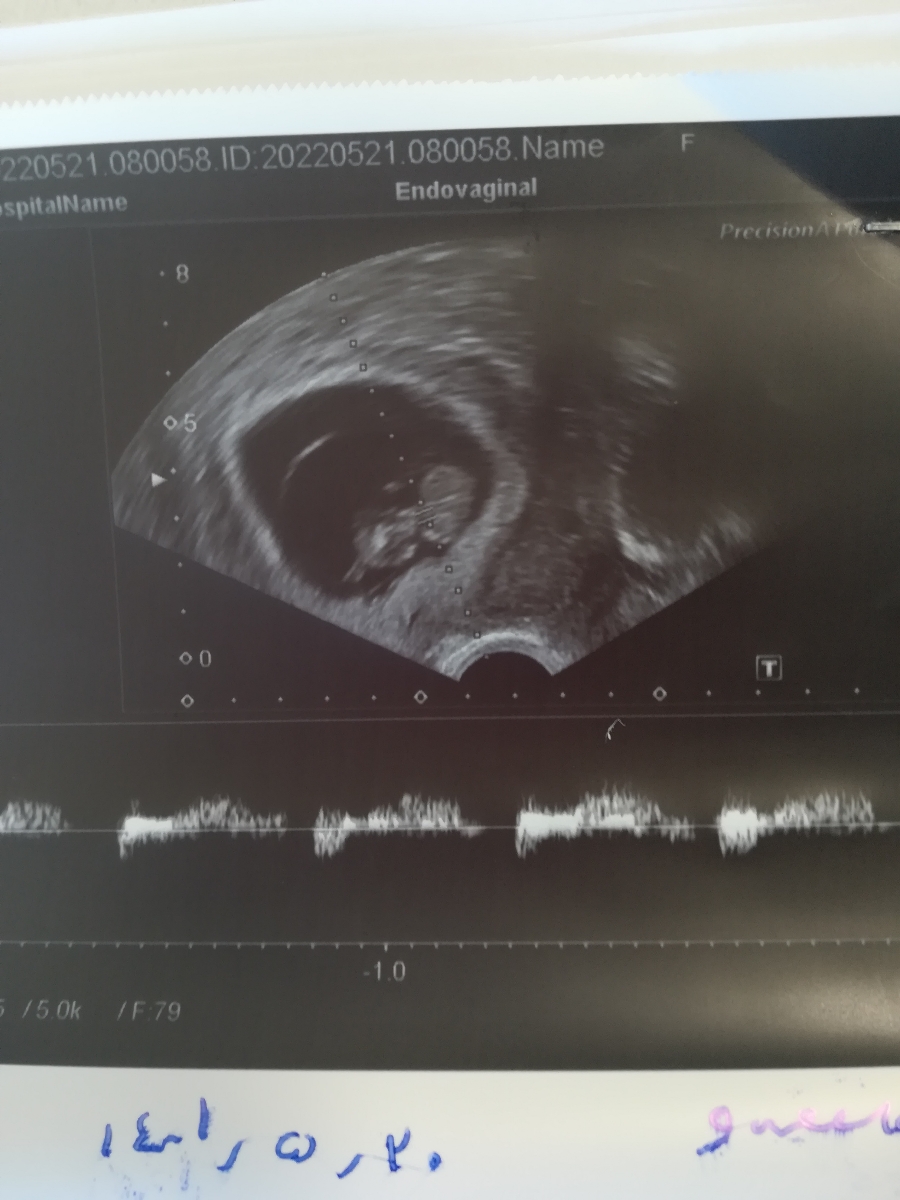

مامان گل، برای انجام غربالگری مرحله اول از ابتدای هفته 11 تا انتهای هفته 13 وقت دارید اما چون الان تعیین دقیق سن بارداری برایتان سخت است، آخرین سونوگرافی و تاریخ انجام آن و اولین روز آخرین قاعدگی را ارسال کنید

آخرین سونو در این تاریخ بوده. 9 هفته و5روز گفتن

اولین روز اخرین قاعدگی 1401/03/08

ممنونم عزیزم، حوالی 5 روز دیگر زمان خوبی برای انجام بررسی ها است 🌹